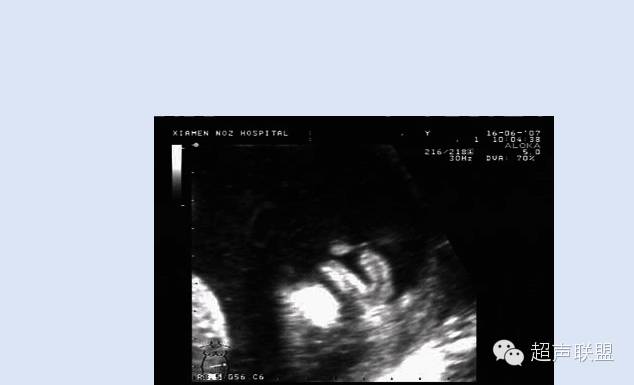

(1) 面部冠状切面和鼻、唇部横切面可清楚显示上唇连续性中断,张口时裂口增大,Ⅱ度唇裂时鼻结构正常,Ⅲ度唇裂时鼻结构失去正常形态,两侧鼻孔不对称,患侧鼻翼内陷。

(2) 合并腭裂时鼻腔与口腔相通连,牙槽突回声不连续。舌活动幅度大。